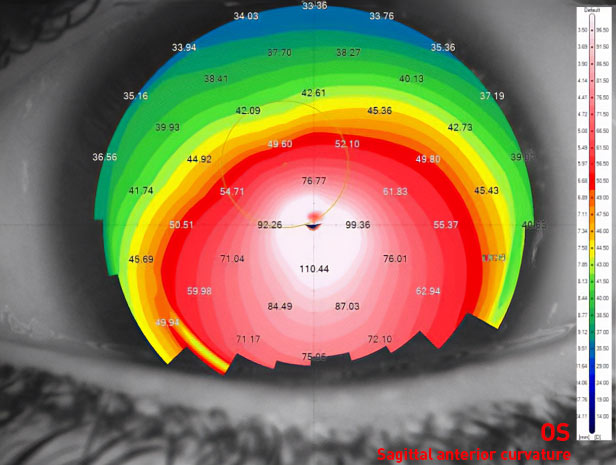

Im Jahr 2019 kam eine Patientin zu uns, die eine zweite Meinung einholen wollte. Sie litt an Keratokonus - einer Erkrankung, bei der sich die Hornhaut, die klare Vorderfläche des Auges, verdünnt und zu einer kegelförmigen Form vorwölbt. Ihr spezieller Fall war eine besondere Herausforderung. Das rechte Auge wies einen Kmax von mehr als 150 D (Radius 2,15 mm) und eine Hornhautdicke von nur etwa 160 Mikron auf. Mit anderen Worten, die Patientin hatte ein sehr fortgeschrittenes Stadium des Keratokonus: einen sehr steilen Kegel und eine sehr dünne Hornhaut. In vielen Kliniken würde ein Arzt diese Hornhaut sehen und sofort mit der Planung einer Hornhauttransplantation beginnen - mit all den Risiken und Herausforderungen, die dieser Eingriff mit sich bringt.